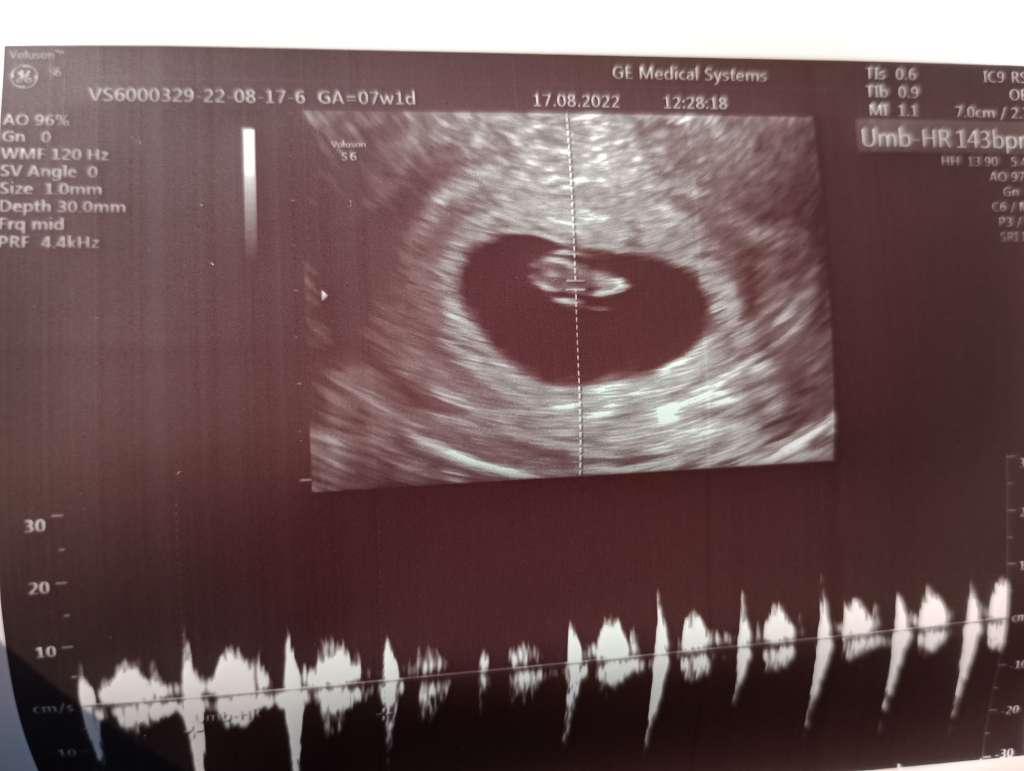

Byłam na przyśpieszonej wizycie u mojej gin (miałam mieć 25.08 ale jej coś wypadło i dzwoniła przesunąć). Jak na ten moment wszystko idealnie. W czwartek nawet zarodka nie było, dziś już ponad centymetr ma i serducho ładnie, miarowo bije :)

Załączniki

• 9220cc28-9fdb-4133-ad56-39ef445cae58.jpeg

9220cc28-9fdb-4133-ad56-39ef445cae58.jpeg

49,1 KB · Wyświetleń: 102